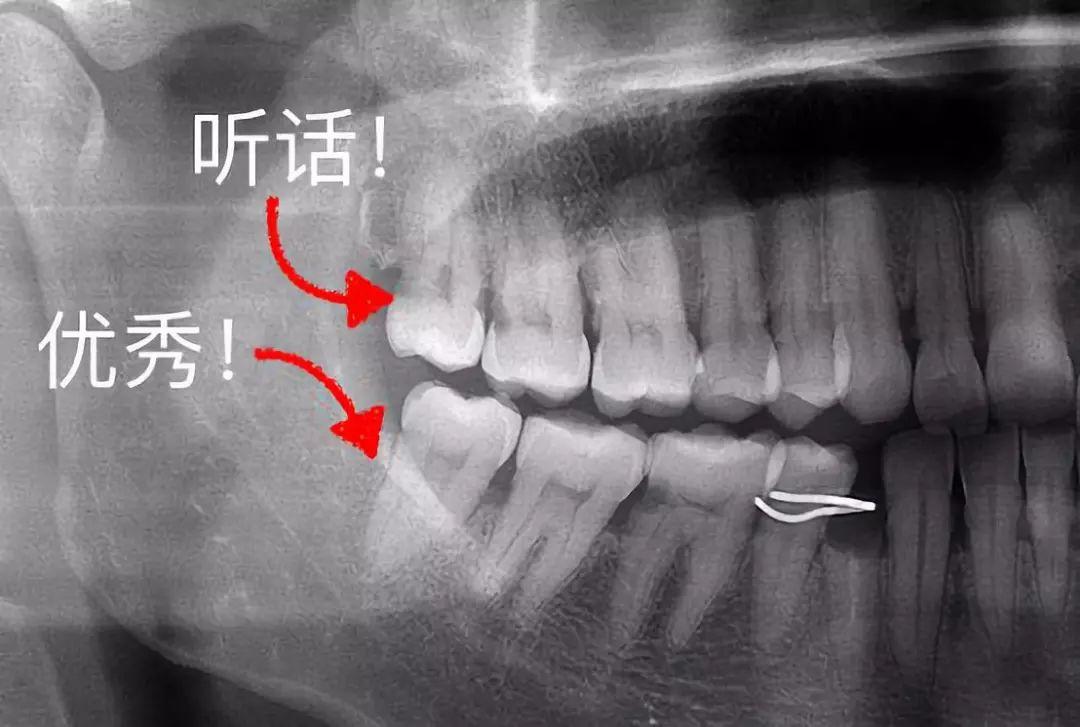

3、這些「聽話」的智齒不用拔

有一些特別乖的智齒,整整齊齊長出來,上下可以咬合,也沒有什么蛀牙,平時都能刷干凈。那么,這種、聽話的智齒完全可以留下,成為咀嚼食物的工具。

整齊、正位萌出的智齒

▼

▍來源:何劍亮醫(yī)生